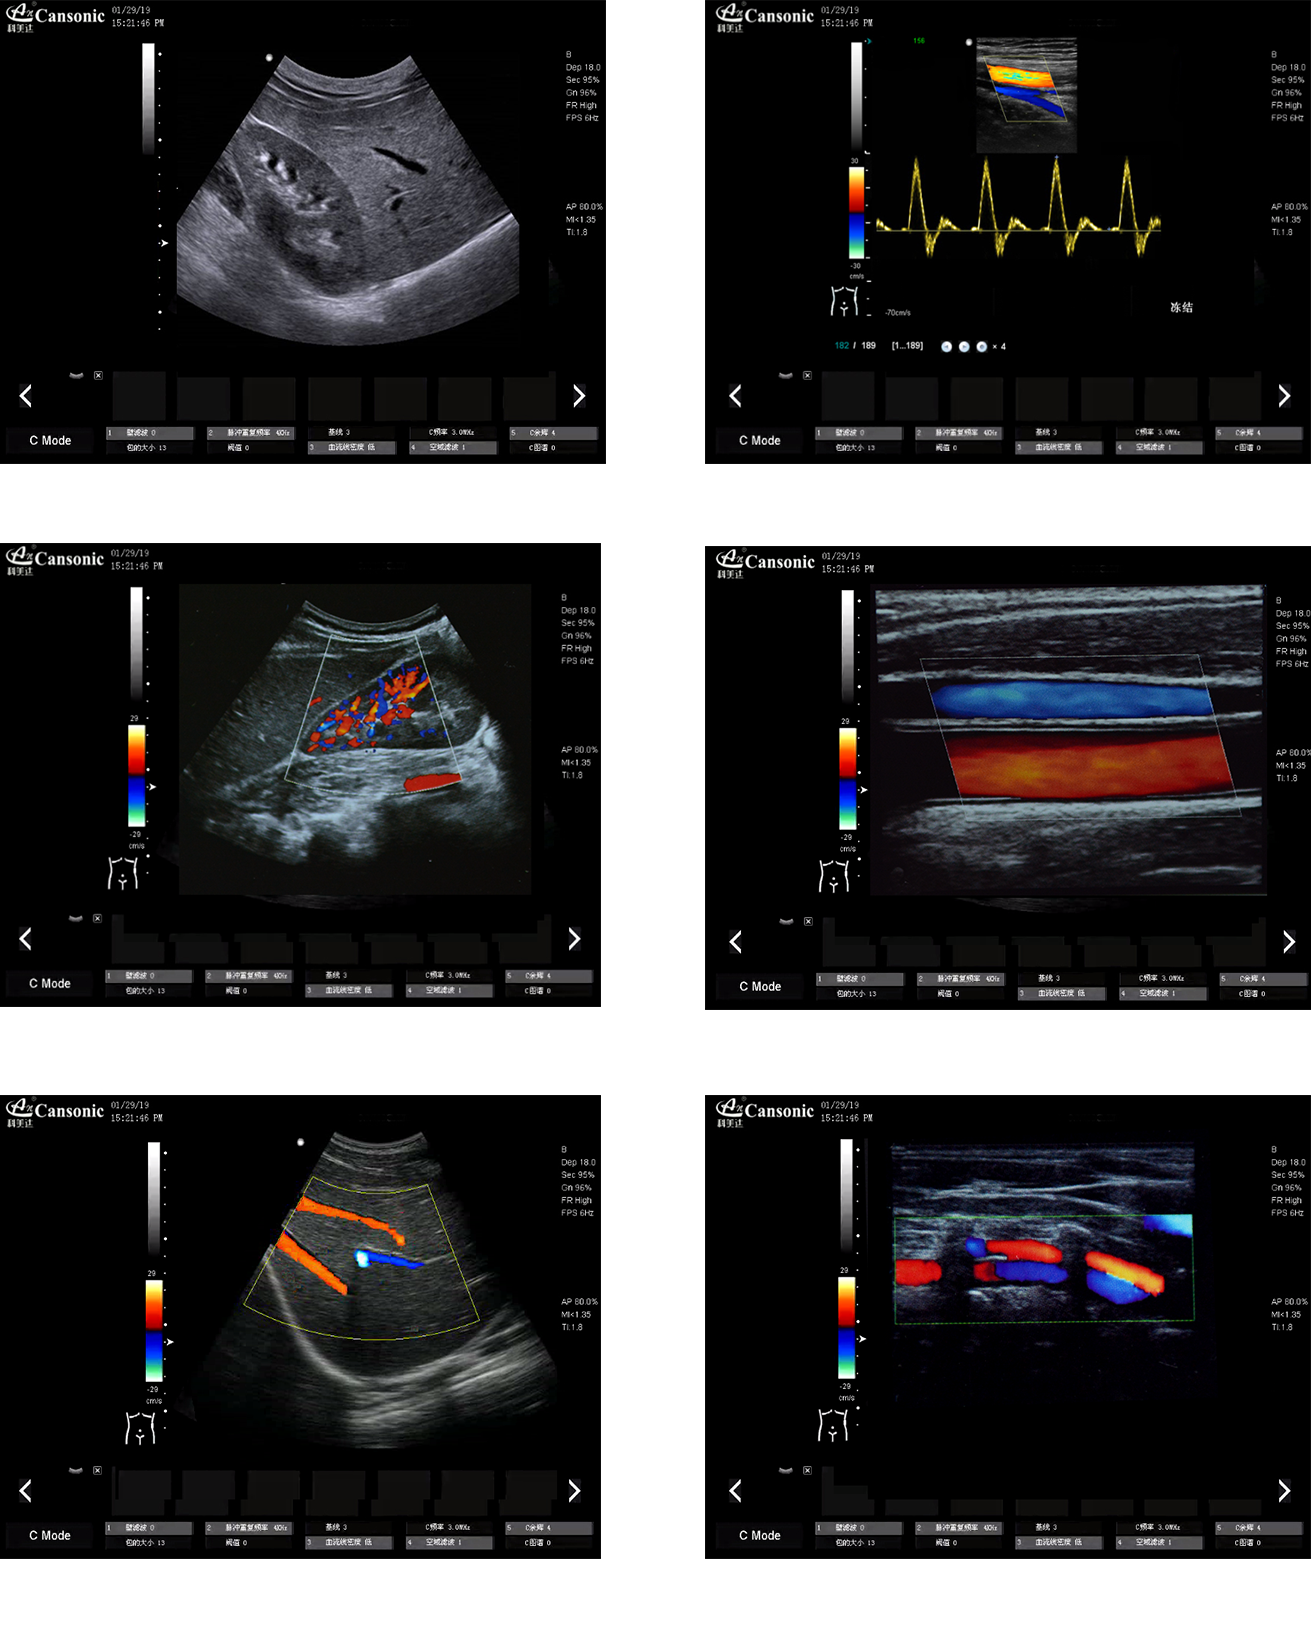

科美達K18圖像實例